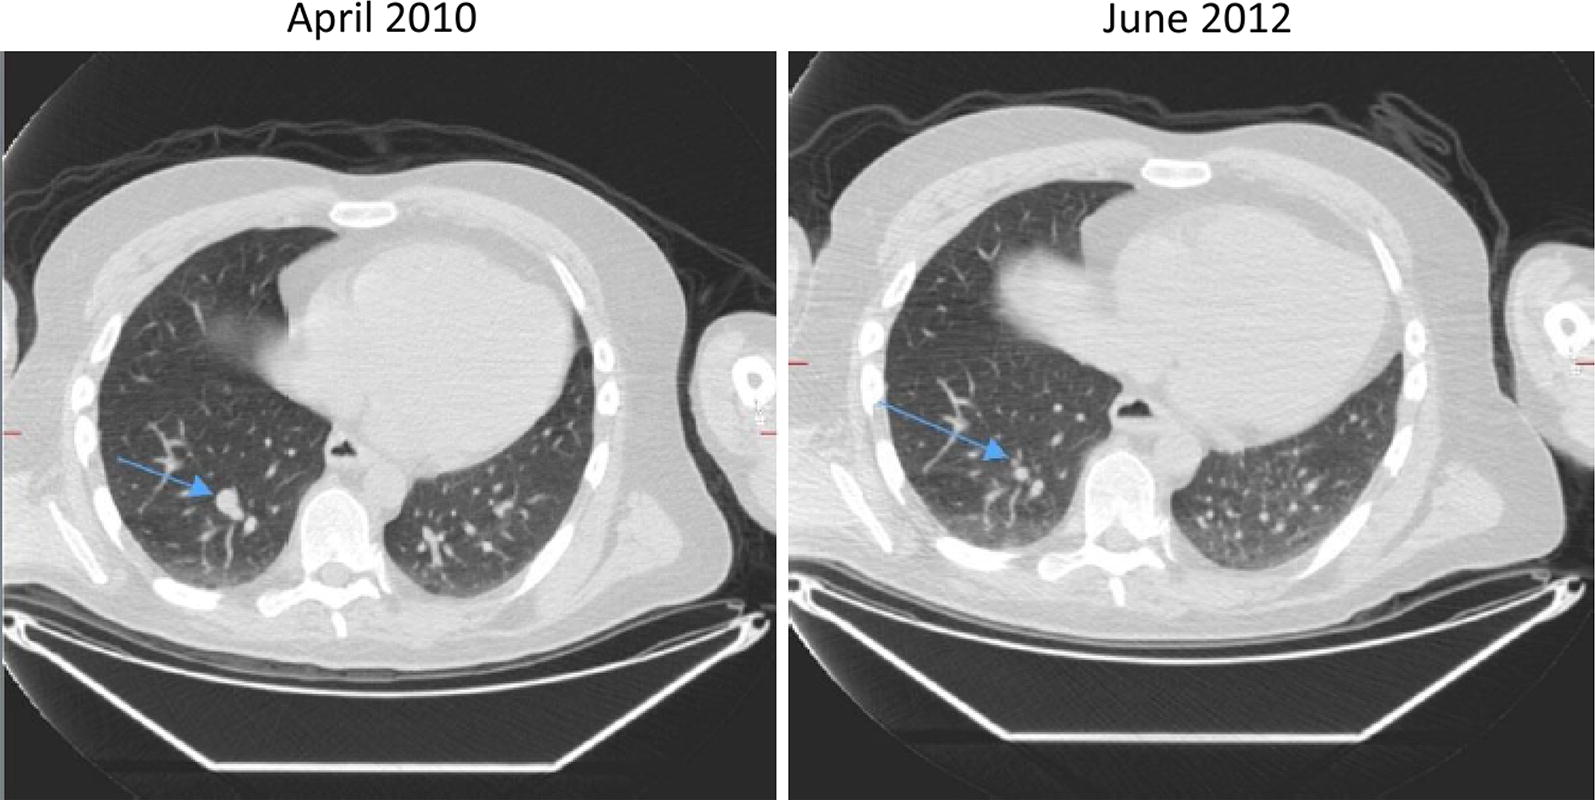

Patient 3

A 79 year-old male presented in 2014 with a melanoma on his left cheek (BT 2.4 mm, not ulcerated, BRAF wild-type) with a positive SNB leading to left neck dissection at time of diagnosis (no further positive nodes). Within months he developed paracardiac nodes, adrenal, lung and multiple large subcutaneous metastatic deposits. In view of his age and performance status he was commenced on IMM-101 on a named-patient program with initial stabilisation of disease. Upon progression of the subcutaneous disease he stopped IMM-101 and started with pembrolizumab, which showed a very rapid benefit as the subcutaneous lesions started to shrink within 4 days of the first infusion (Fig. 2). All visceral disease had also responded as seen on a restaging CT scan performed 6 weeks later with a PR > 50% as per RECIST1.1 criteria initially followed by a CR a few months afterwards (Fig. 3) upon continuation of pembrolizumab which lasted for 18 months and is still ongoing.

Fig. 3.

Complete reponse observed in a 79 year-old male with stage IV melanoma treated with IMM-101 followed by pembrolizumab (lung disease)

In the above mentioned preclinical studies IMM-101 has shown to stimulate an immune response suppressed by the underlying tumour, which may enhance responses to other modalities of treatment. Altogether 11 patients with metastatic melanoma have been treated with IMM-101 and CPIs either sequentially or concomitantly. Despite the majority of these patients were previously pre-treated, about the half of them experienced some kind of benefit. Four of them had an exceptionally good and rapid response and have been presented here. The CR rate with ipilimumab in melanoma is less than 3%. We reported 2 cases that had both received prior IMM-101 treatment and experienced a very good response with ipilimumab; one CR which lasted for a couple of years until unexpected trauma and the other with no new disease for 5 years. Although the CR for PD-1 inhibitors is higher, complete responses may take months before they become manifest. Here we presented a case of widespread stage IV M1c disease that had, following prior IMM-101 treatment, an objective response observed 4 days after the first infusion with the anti-PD1 antibody pembrolizumab and another case of a rapid complete response to treatment when IMM-101 was given in combination with the anti-PD1 antibody nivolumab.